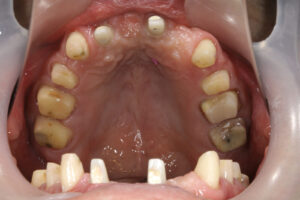

上の前歯が自然に抜けた 40歳男性

H28.12.

大阪市福島区

40歳男性

初診日 2016. 12.  (5年経過症例)

患者様の症状

1年前から他の歯科医院にて部分的な治療を受けたが、どんどん歯が悪くなって、見た目が良くない・噛めないとのことで再治療を希望された。昨日、上の前歯が自然に取れた、他の医院に行こうとしたところ知人に当医院を勧められ来院した。アングルクラスⅡであった。

治療法

全顎的に歯周病が進行し、ほとんどの歯に動揺が見られた。アングルクラスⅢで下顎前歯部に叢生が見られ、全顎の再生療法の後に、全顎的にオールセラミッククラウンを装着し、既存の被せのやり直しを行なった。